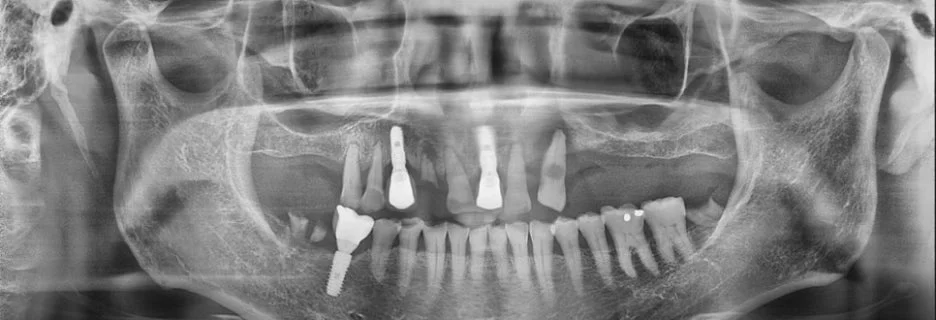

첫 방문 당시 촬영한 사진을 보면, 어금니 부분이 비어 있고 앞쪽에만 임플란트가 시술된 상태였던 것으로 보였습니다.

영상 촬영 결과를 살펴보면, 임플란트를 하기 어려울 정도로 뼈가 부족해 보이지는 않았습니다. 그럼에도 다른 치과에서는 임플란트가 어렵다는 이유로 틀니를 권유받으셨다고 합니다.